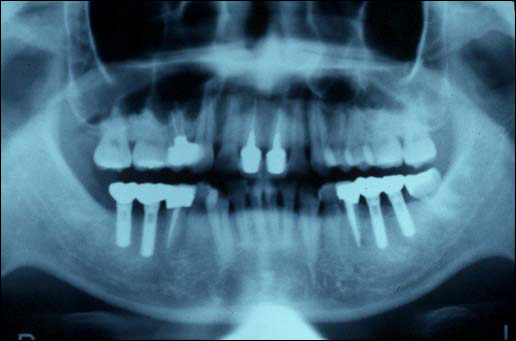

【インプラント】

歯を失ったところに人工の歯をいれる治療を歯科インプラント治療といいます。最近では、インプラント治療は急速に進歩しています。当院では積極的にインプラント治療を行っています。

インプラント治療後